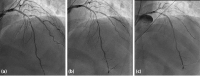

OCT

Abbildung 3: OCT run after NC dilatation: (a) Significant deep medial dissection starting < 5 mm from distal stent edge with apparent inlet. In L-Mode flap appears long and significantly protruding with risk of lumen occlusion (* = wire artifact). (b) Intramural hematoma (separation of IEL and EEL) from 12 to 3 o’clock and lipidic plaque from 6 to 9 o’clock and significant luminal narrowing. (c) Hematoma is partially evacuated after NC-ballooning.